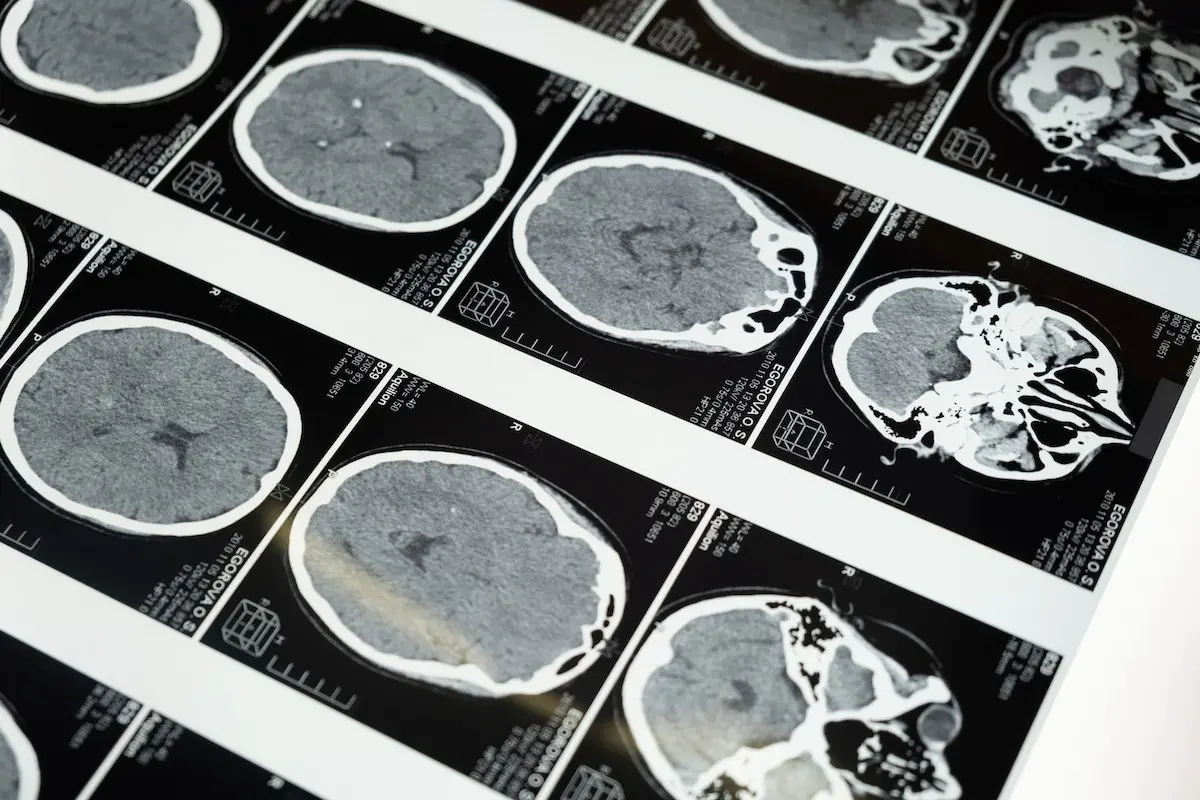

Neurological disorders, ranging from mild traumatic brain injuries (mTBI) and post-traumatic stress (PTSD) to Alzheimer’s disease and Parkinson’s disease, have long posed significant challenges for patients and healthcare professionals alike. In the search for effective treatments, hyperbaric oxygen therapy (HBOT) has emerged as a beacon of hope. Research suggests that HBOT may serve as a valuable adjunctive therapy for a wide spectrum of neurological conditions.

- Mild Traumatic Brain Injury (mTBI) and Post-Traumatic Stress (PTSD): Studies and case reports have explored the use of HBOT for individuals with mTBI and PTSD. This research suggests that HBOT could help improve cognitive function and alleviate post-concussive symptoms.

- Anoxic Brain Injury / Near Drowning: HBOT has been examined as a treatment option for individuals who have experienced anoxic brain injury, such as near-drowning incidents. Case reports have demonstrated positive outcomes, including the reversal of brain volume loss.